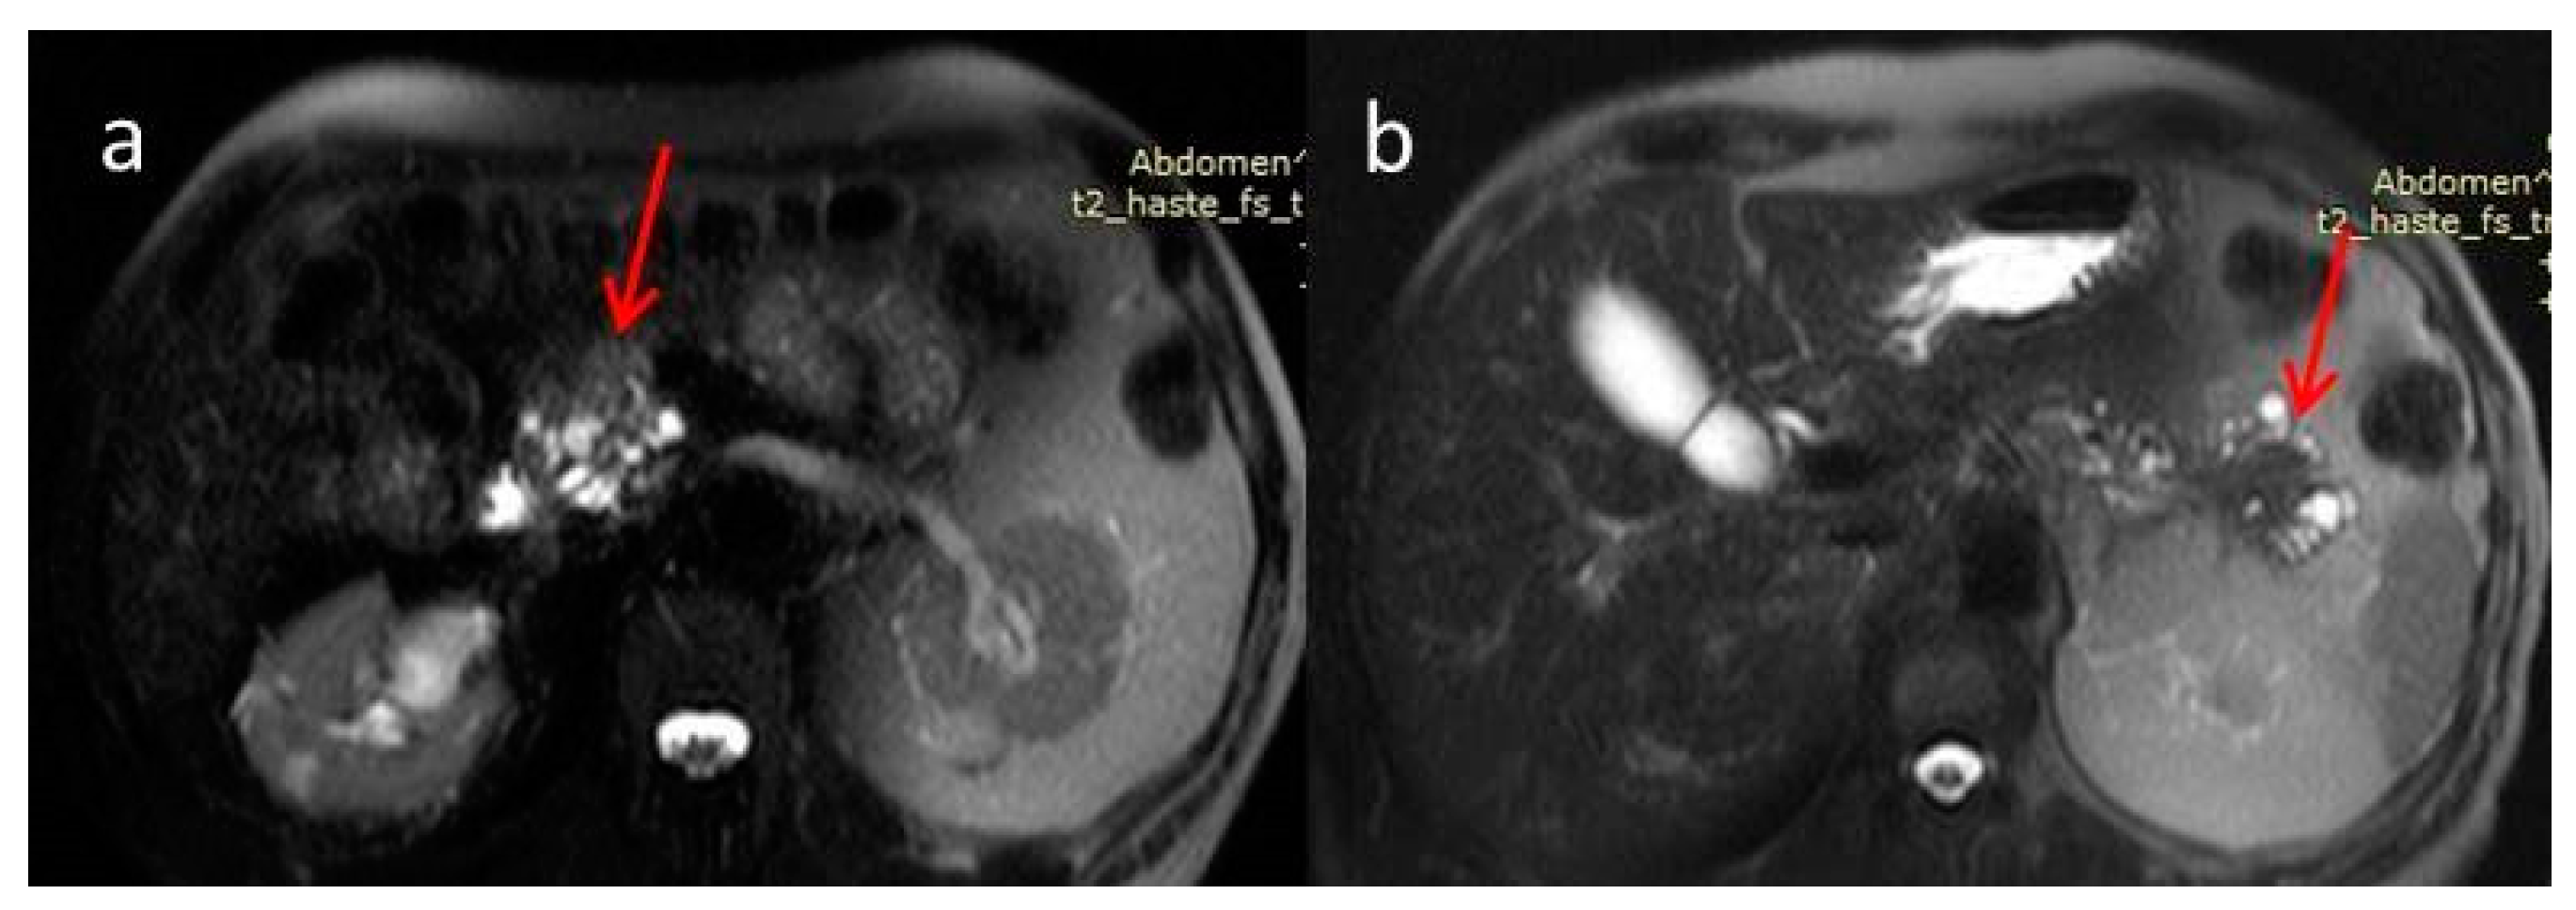

2. Case Report